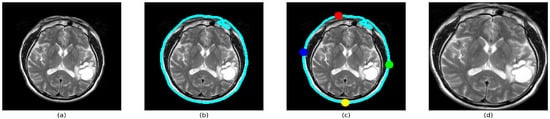

The next step consists of image pre-processing. We aim to remove additional data present around the main MRI brain scan, making sure that all the images are of the same type, and the focus is only on the central part of the brain. To carry out the mentioned preprocessing, we have used a relatively common method of using the extreme points of a contour. The simple step by step approach illustrated in Figure 2, combined with a few image processing methods such as converting the image to Grayscale, Thresholding, and Opening (Erosion followed by Dilation), as mentioned below in Algorithm 1, makes sure that the brain is in focus in each image. Finally, using the extreme points as a mask, it is a fairly simple task to crop out the parts of the image that do not add any value to the classifier model.

Figure 2.

(a) Original Image: Section of brain from a MRI scan (b) Finding largest contour: Detecting the overall shape of the skull structure. (c) Calculating extreme points of contour: Selecting the best points to fit the entire brain into the frame with minimum loss of data (d) Cropping based on extreme points: The brain structure from the MRI image is the main focus area of the new image.